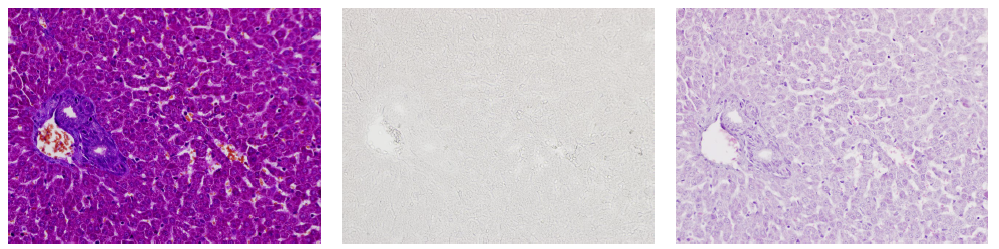

使用小鼠肝臟標(biāo)本進(jìn)行MT染色時

使用deColorizing Solution 1和2進(jìn)行脫色

左至右:MT染色→脫色→HE染色

(數(shù)據(jù)提供:麻布大學(xué)小澤秋沙先生、坂上元榮先生)